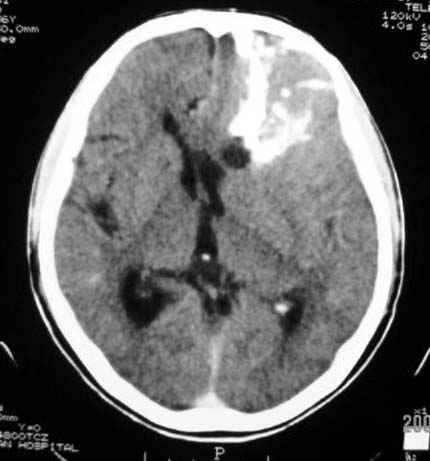

标题: CT7268:左额顶部病变增强片. [打印本页]

标题: CT7268:左额顶部病变增强片.

比较典型的少枝胶质细胞瘤ct表现,局部额骨垂直板有侵蚀变薄。

左额叶病灶内条片状高密度是钙化吗?是的话考虑少支胶质瘤可能大。不然有脑血畸形伴出血可能。

左侧额顶叶有条带状钙化的不规则形占位,增强呈不均匀轻度强化,局部颅骨受侵蚀变薄,典型的少支胶质细胞瘤。

比较典型的少枝胶质细胞瘤ct表现,局部额骨垂直板有侵蚀变薄